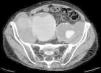

Paciente varón de 86 años, hipertenso en tratamiento con 2 fármacos, con historia de dolor lumbar con irradiación crural derecha de varios meses de evolución que se había controlado parcialmente con tratamiento sintomático. Su reumatólogo le había prescrito RM dorsolumbar que no llegó a realizarse ya que el paciente acudió antes a urgencias por aumento de la intensidad del dolor. En la analítica, hemoglobina 8,4g/dl, LDH 318 U/l, creatinina 1,29mg/dl, PCR 6,16mg/dl, VSG 24mm/h y leve hipoproteinemia. Ausencia de signos de inestabilidad hemodinámica. Se realizó una TC abdominopélvica con contraste por vía intravenosa que muestra aneurismas ilíacos aislados bilaterales>6cm (fig. 1) con rotura contenida del derecho (fig. 2), que desplazaba el músculo psoas (fig. 3) y horadaba el hueso ilíaco ipsolateral (fig. 4). El paciente es sometido a by-pass aortobifemoral pero lamentablemente fallece en el postoperatorio.

Los aneurismas ilíacos aislados, sin aneurisma aórtico asociado, son raros1. Son relativamente difíciles de identificar, ya que hasta un 40% de ellos se pueden presentar con rotura2. La tasa de incidencia de causas extraespinales de ciática es baja3. Igualmente, el aneurisma roto crónico constituye una entidad peculiar. Todas estas circunstancias se aúnan para que el diagnóstico, la mayoría de las veces, sea erróneo y tardío4. Suele tratarse de una rotura laterodorsal hacia las inserciones anteriores del psoas que contiene el hematoma, evitando la extravasación masiva pero no la infiltración de las raíces del plexo lumbosacro, lo que origina un dolor crónico lumbar con irradiación al miembro inferior5, siendo esta su presentación más frecuente6. El diagnóstico puede realizarse con TC abdominal7, pudiendo también visualizarse en la RM lumbar (corte parasagital)7,8. En cualquier momento de la evolución, el aneurisma puede sufrir una rotura aguda secundaria4. Este caso sirve para recordarnos, en nuestra práctica diaria, que la causa aneurismática puede estar implicada en los síntomas de ciática9.